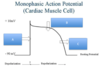

What does this ECG show and why?

S-T depression, can be sign of chronic ischaemia